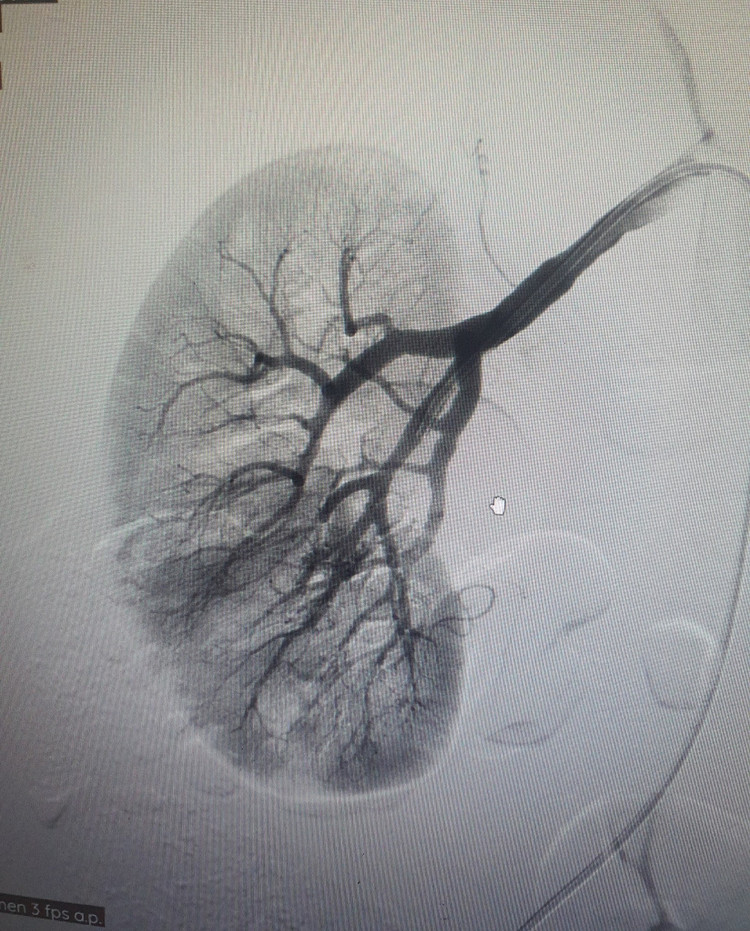

Ca can thiệp được thực hiện tại trung tâm Tim mạch - điện quang can thiệp Bệnh viện Đa khoa Hùng Vương diễn ra thuận lợi, bệnh nhân tỉnh táo trong suốt quá trình can thiệp, không đau đớn. Các bác sĩ đã thực hiện can thiệp nút tắc ổ dị dạng thông động - tĩnh mạch bằng keo sinh học.

Trước đây, AVM thận phải thực hiện phẫu thuật cắt thận bán phần hoặc toàn bộ để xử trí ổ dị dạng, tuy nhiên, đây là phương pháp rất nặng nề, bệnh nhân phải trải qua cuộc mổ đau đớn, hồi phục chậm, điều trị kéo dài. Với kỹ thuật can thiệp nút mạch sẽ giúp bảo tồn tối đa nhu mô thận lành, hạn chế thấp nhất biến chứng, bệnh nhân điều trị nhẹ nhàng, hồi phục nhanh, tiết kiệm chi phí và thời gian điều trị.

| Thăm khám cho bệnh nhân sau can thiệp |

Triệu chứng chủ yếu của bệnh AVM là bệnh nhân bị đau thắt lưng, nặng hơn là tiểu ra máu do cục máu đông tắc nghẽn trong đường bài xuất. Tiểu máu nhiều có thể đe dọa tính mạng người bệnh. Vì vậy, người dân khi có các triệu chứng: đau thắt lưng, tiểu ra máu… nên đi đến các cơ sở y tế để được thăm khám, chẩn đoán và điều trị kịp thời.